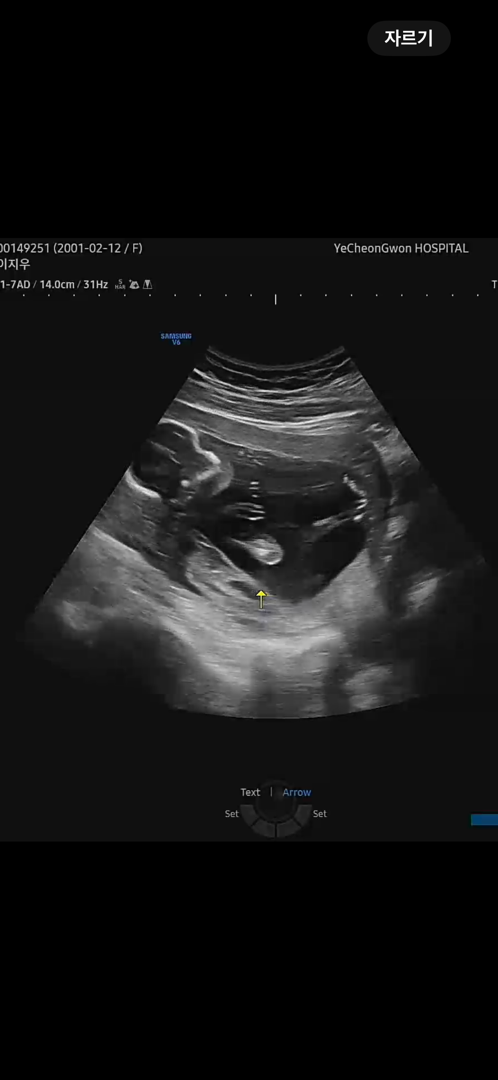

여러분들은 혹시 성별 확정적으로 나오셨을까요?! 저는 15주때 병원 갔는데 잘 안보이고 모르겠다고만 듣고 집에 돌아왔어요ㅠㅠ보통 아이의 성별이 확정이되는 시기는 어느정도일까요?!

보통은 16주 이상되면 알수있다고 알고있는데요 아기가 잘안 보여주거나 확실하지 않는경우 20주에 확정 된다고 하더라구여 애바애 인거 같아요 저는 15주에 배가 아파서 병원갔다가 아기가 너무나 잘 보여줘서 반전 없을거라며 딸랑구 확정 받고 왔어요🥺

저 16주에 99프로 아들 나왓어욤 너무 존재감뿜뿜...ㅎ

남자 아가는 기형아검사할쯤부터 존재감이 확실해서 거의 확정이라고 말씀주시던데, 여자 아가는 20주 이상 되어야 확정 말씀주신다더라구용